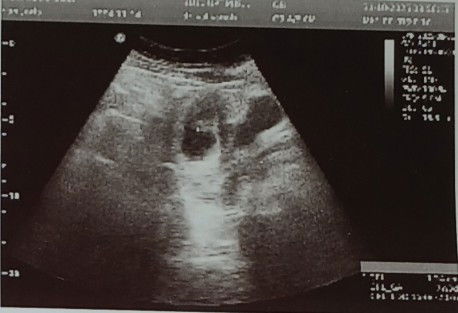

Ini usg 7 minggu tapi ko itu gambar nya begitu ada yang ngerti lihat hasil usg gak? Dari gambar nya

Itu pinggir nya gambar apa?

kalau awal kehamilan memang begitu bund.. belum jelas kelihatan si dedek nya soalnya ukuran nya masih kecil 😁 tapi tetap akan terdeteksi kok ada si dedek dan kantung kehamilan nya ☺️

dari penjelasan dokter bagaimana Bun katanya??